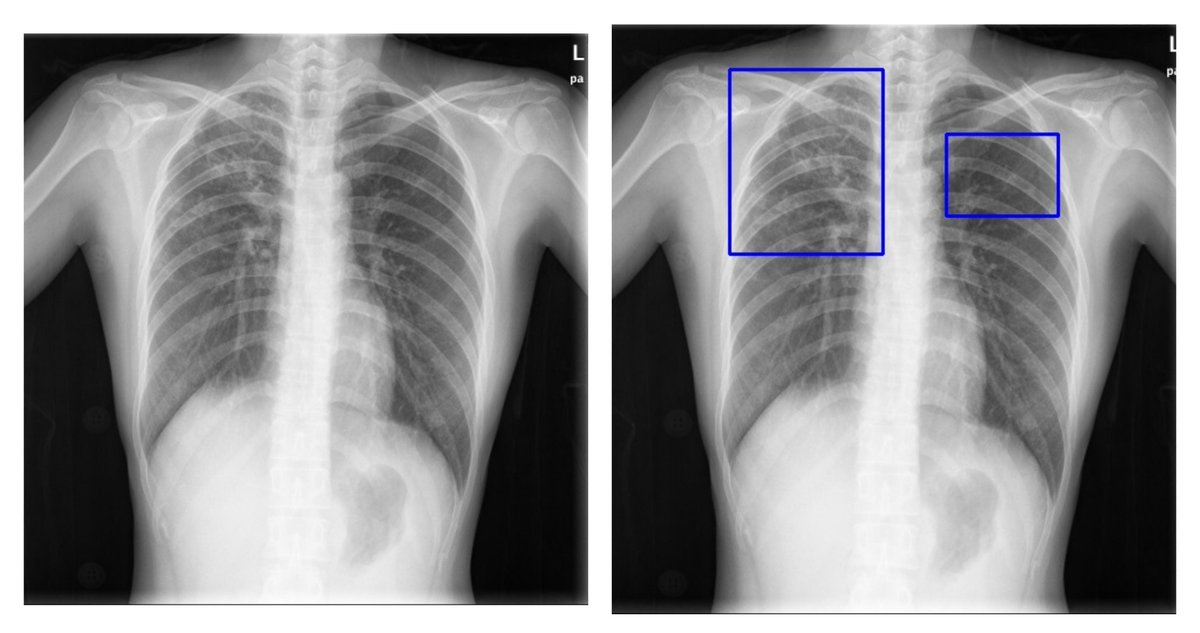

At Easiofy, three women engineers built ImagiXAI to speed cancer planning and bring advanced imaging to remote India.